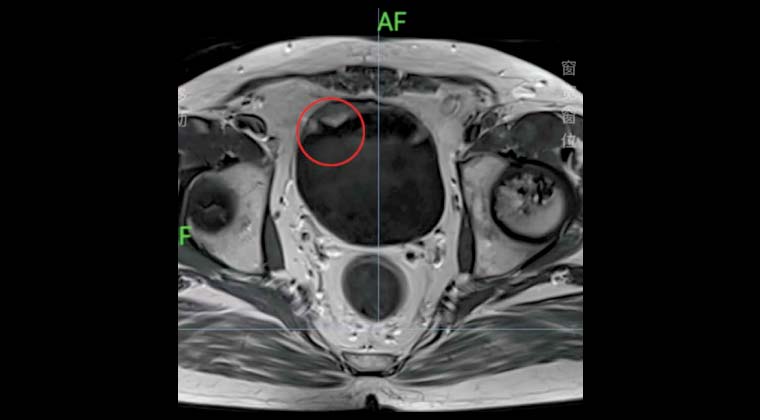

Пациент мужского пола, 54 года

Злокачественная опухоль мочевого пузыря

В феврале 2024 года у пациента наблюдалась макрогематурия, сопровождавшаяся учащенным, срочным и болезненным мочеиспусканием. Обследование в местной больнице подтвердило злокачественную опухоль мочевого пузыря, выявлена уротелиальная карцинома высокой степени злокачественности. Было рекомендовано хирургическое удаление, но пациент отказался.

С 21 марта по 25 апреля 2024 года пациент проходил в нашей клинике синхронную точную лучевую терапию опухоли мочевого пузыря с локальной гипертермией. Последующее наблюдение показало отсутствие рецидива до настоящего времени.

Левое изображение: до лечения

Правое изображение: после лечения